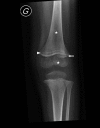

We report 3 cases of scurvy in children that occurred during a short period (2018) in a general pediatrics unit of a tertiary hospital for children in Paris. All children were around 3 years of age and were admitted for skeletal pain and altered general state, which mimicked infectious or malignant diseases. Their selective diet was not the prominent issue. The diagnosis of scurvy was delayed, after too many unnecessary examinations and medications. Bone imaging findings (X-ray and MRI) were a posteriori considered typical, but lesions were not easily identified as scurvy lesions because scurvy is not well-known by pediatricians and radiologists who should be mindful of this historical diagnosis VSports手机版. .